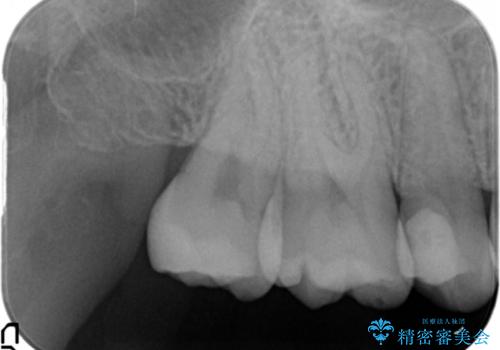

- 上の奥の虫歯をセラミックインレーで修復しました。

特に自費のインレーの適合(歯にぴったり合っている)はとても良く、虫歯になりにくいです。

高価なようで、実は将来のことを考えた歯を残す治療の第一歩です。